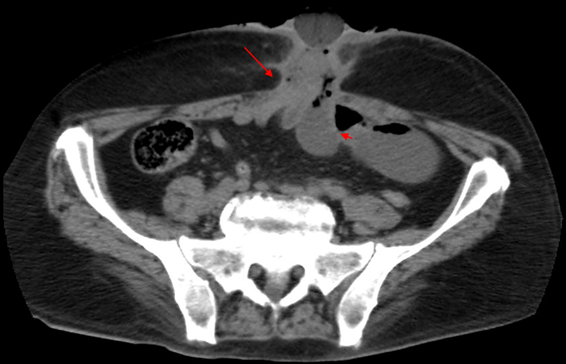

Foto 2 Corte axial de tomografía de abdomen contrastada con evidencia de fistula enterocutánea. (Flecha: indica la fistula entero-cutánea; Cabeza de Flecha; indica el conglomerado de asas intestinales

A la exploración física se observó pérdida de continuidad de 1 cm en la cicatriz previa, con secreción purulenta y dolor sin evidencia de irritación peritoneal. Se realizó radiografía simple de abdomen, (Foto 1) y tomografía de abdomen (Foto 2), ambas con datos sugestivos de oclusión intestinal; la tomografía documentó fístula enterocutánea, por fuga de medio de contraste a través de pared abdominal.